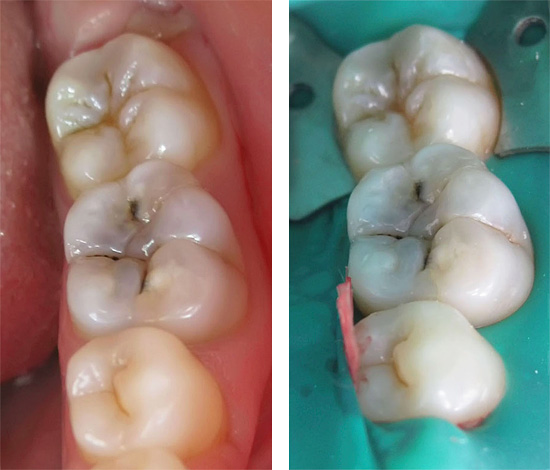

Ed è così che appare il trattamento della carie profonda al microscopio, tutti gli stadi sono ben tracciati